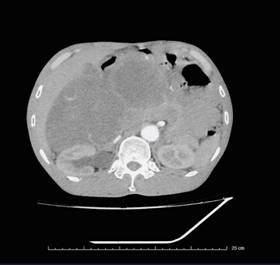

Quá trình chẩn đoán, qua chụp cắt lớp vi tính ổ bụng có hình ảnh khối u dạng đặc chiếm gần hết ổ bụng chủ yếu vùng bụng bên phải, chưa xâm lấn mạch máu lớn. Trên nội soi đường tiêu hoá thì khối u từ ngoài đẩy vào lòng đại tràng lên.

Khối u lớn khoang sau phúc mạc cạnh trước thận phải kích thước 233x191x141mm, bờ gọn, lan sang khoang cạnh trước thận trái, đè ép niệu quản phải gây giãn nhẹ đài bể thận phải, ngấm thuốc sau tiêm - Ảnh BVCC